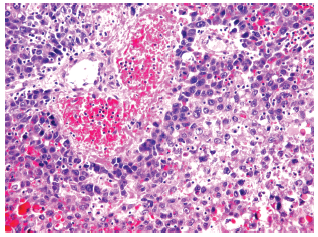

The study group included 14 patients with HCC and liver cirrhosis (45.2%) (Figure 1) and 17 patients with HCC without liver cirrhosis (54.8%) (Figure 2). The control group (patients with chronic liver disease) included 12 patients with liver fibrosis (44.5%), 7 patients with primary biliary cirrhosis (25.9%), 3 patients with autoimmune hepatitis (11.1%), and 5 patients with cirrhosis due to other causes (18.5%).

Morphologic data were characterized for signs of HCC. Trabecular-type HCC was predominant, shown in 26 patients (83.9%),versus solid tumor type, shown in 5 patients (16.1%). Degree of malignancy according to the Edmondson-Steiner system showed 8 patients (25.8%) having grade I, 10 patients (32.3%) having grade II, 9 patients (29.0%) having grade III, and 4 patients (12.9%) having grade IV (Figures 3-6 show resection of archived materials).

Figure 1. Hepatocellular Carcinoma and Liver Cirrhosis

Figure 3. Hepatocellular Carcinoma, Showing Adenoma-Like Variant With Marked Fibrosis Fields (6 points) (hematoxylin and eosin staining; ×200)